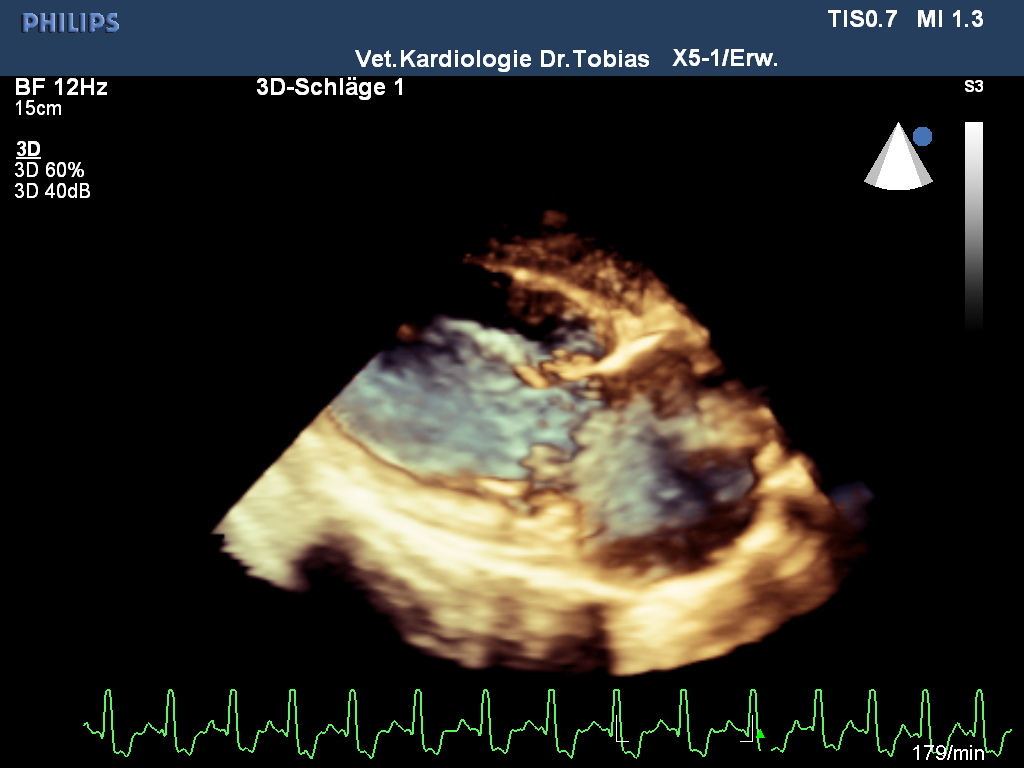

Neben der Auskultation und dem Röntgen stehen dem Veterinärkardiologen die gleichen Untersuchungsmethoden zur Verfügung, wie sie auch in der Humanmedizin Anwendung finden: das Elektrokardiogramm erlaubt eine Rhythmus und Frequenzanalyse, die Blutdruckmessung ist ungleich schwieriger als in der Humanmedizin und spielt bei Katzen eine größere Rolle als beim Hund, das Fundament der Kardiologie ist die Herzultraschalluntersuchung, die den Sitz und die Charakterisierung der Krankheit erlaubt sowie eine Schweregradbestimmung. Zur anatomischen Darstellung werden ein- und zweidimensionale Methoden genutzt, auch 3D- und 4D–Methoden sind in spezialisierten Einrichtungen zu finden. Die Blutflussdarstellung erfolgt mit verschiedenen Dopplermethoden, die viele Hundebesitzerinnen auch aus Schwangerschaftsuntersuchungen kennen. Neuere Methoden zur Herzmuskeluntersuchung sind die Speckle Tracking- und Gewebedopplermethoden.

Rike wurde einer modernen Echokardiographieuntersuchung nach nationalem und internationalem Standard unterzogen und zusätzlich eine 3D/4D-Bildbetrachtung vorgenommen und ihre Herzmuskelleistung via Speckle Tracking untersucht. Die Untersuchung bestätigte eine offene Verbindung zwischen Aorta und Pulmonalrterie, die sich bei der Geburt hätte schließen müssen. Durch die Volumen und Drucküberladung kommt es zu einer Linksherzbelastung, die zu einer deutlichen Vergrößerung der linken Kammer geführt hat. Infolge der Kammervergrößerung wird die linke Vorkammer-Kammerklappe undicht und zunehmend Blut in Richtung Lunge zurücklassen, was das Stauungsrisiko weiter steigert. Typischerweise erhöht sich wie auch bei Rike der Aortendruck, ohne dass anatomische Anzeichen einer Stenose festzustellen wären. In der Pulmonalarterie ist im Farbdoppler ein chaotisch-turbulentes Signal zu sehen, während die Ductusampulle laminar bleibt. Im EKG zeigten sich bereits verlängerte Überleitungszeiten im Kammerkomplex QRS und Senkung des ST-Segmentes, als Zeichen einer Hypoxie des Herzmuskels.